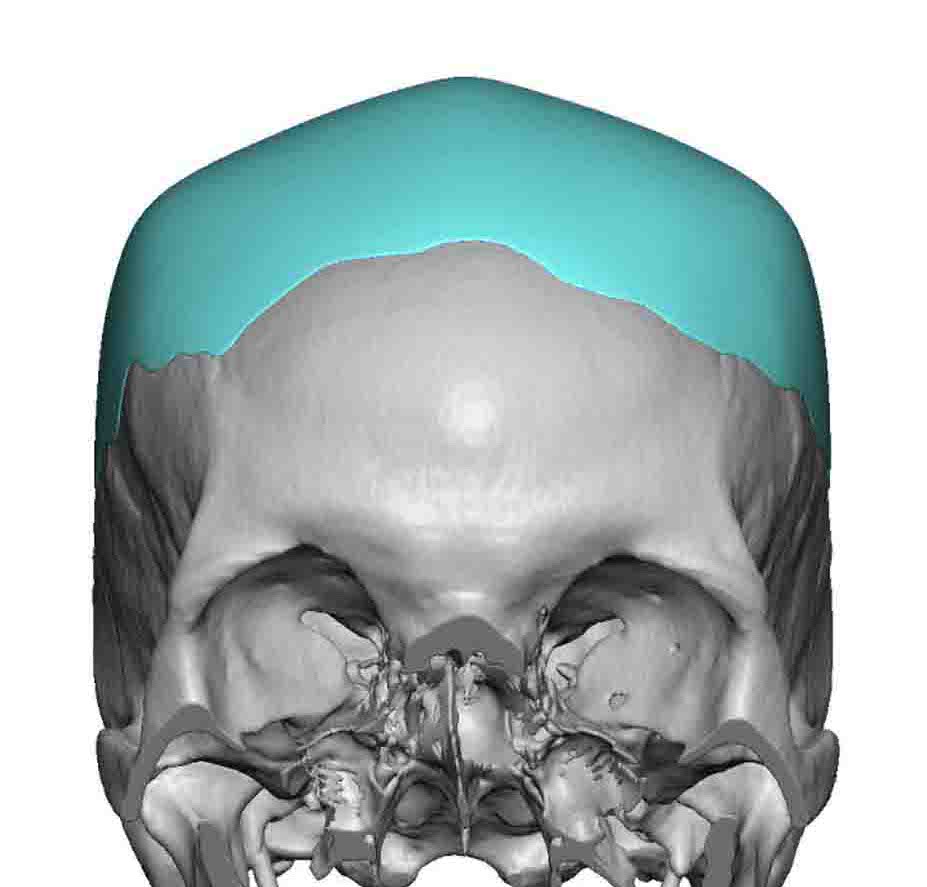

Desire for a higher and more prominent crown of the skull.

Crown of skull augmentation using a custom skull implant.

Desire for a higher and more prominent crown of the skull.

Crown of skull augmentation using a custom skull implant.